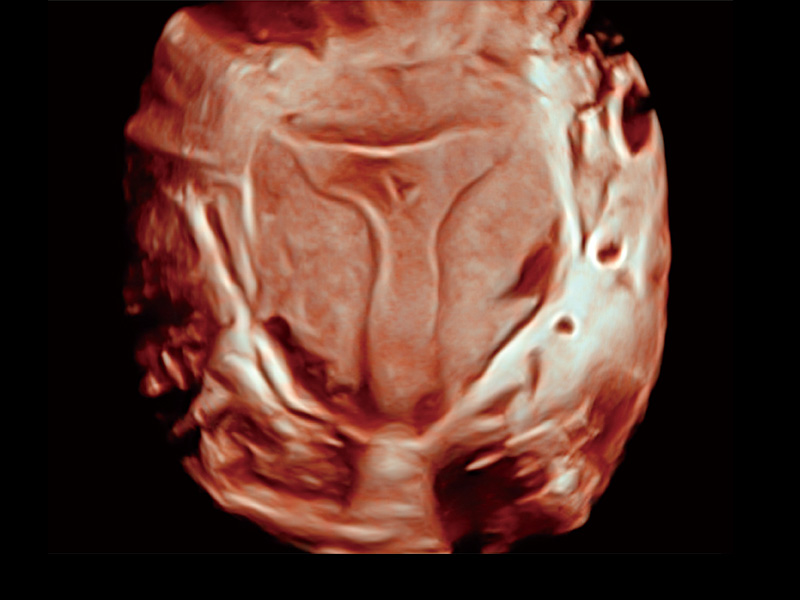

腔内容积探头

腔内三维成像技术获得显著提升,超大扇角在满足日常基础扫查的同时,支持卵泡自动测量及多种三维渲染模式,为您提供更多的诊断信息,尤其是在子宫畸形的诊断,内膜及肿瘤占位观测中起到了重要的作用。

临床图

中央型宫腔粘连